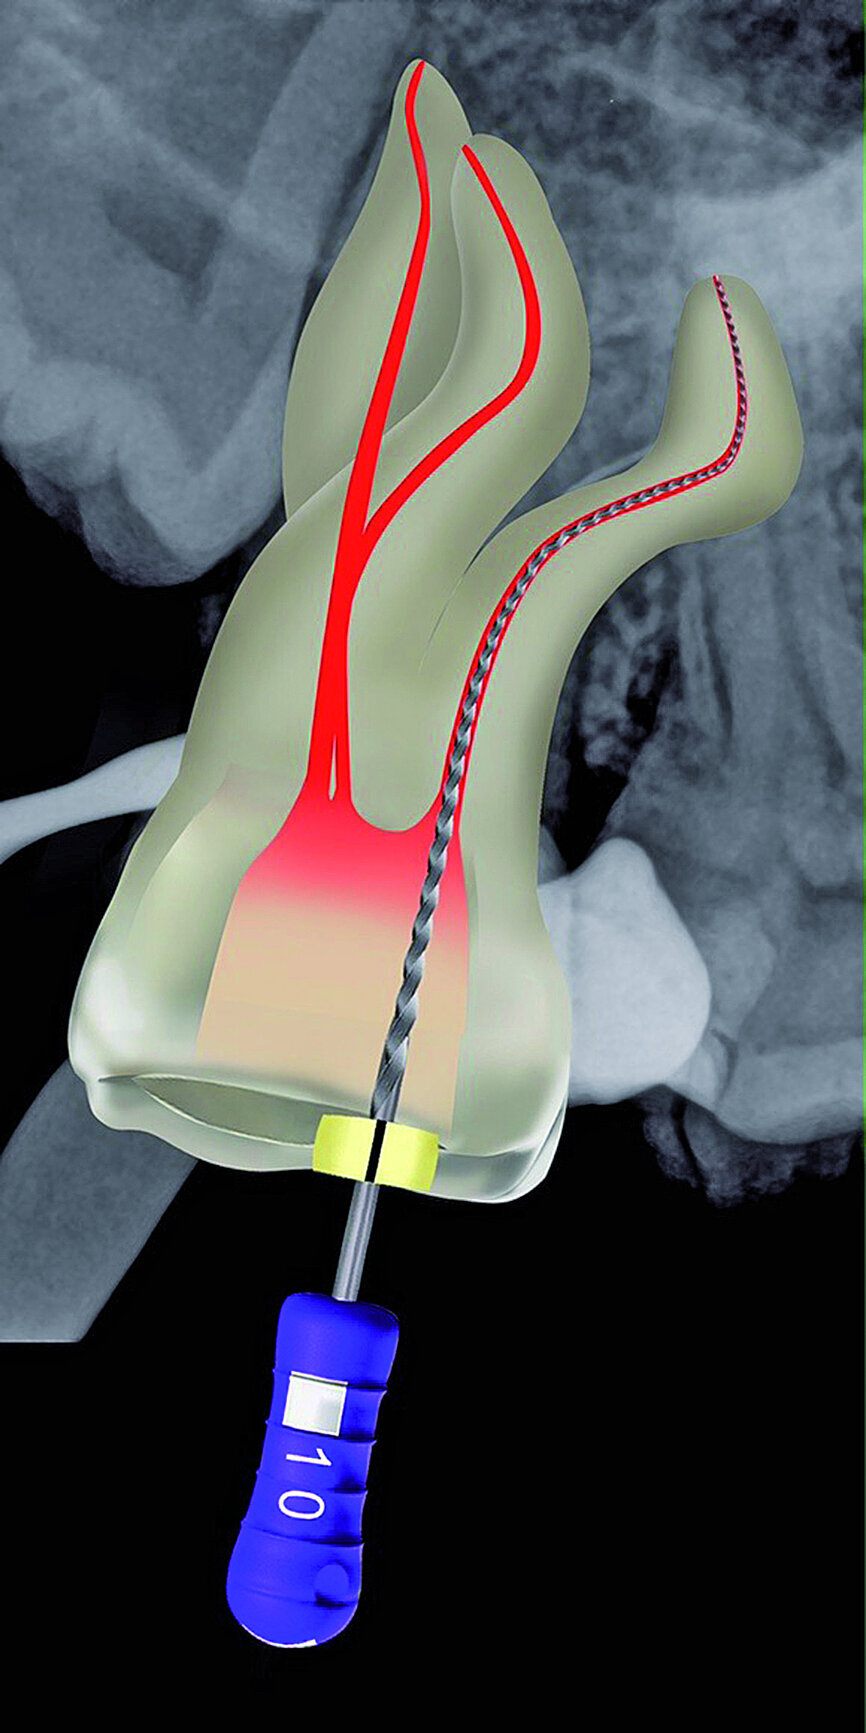

Fig. 22: After the Size 08 K-File, a size 10 K-File was made ‘super loose’ to complete the preparation of the reproducible micro glide path.

The pulp chamber was filled with Glyde (Dentsply Sirona) before the canals were carefully negotiated to full working using pre-curved size 08 K-Files (Fig. 19). Working length measurements obtained from an electronic apex locator reading corresponded with the lengths obtained from the 3D Endo Software. These measurements were also confirmed radiographically (Fig. 20). A reproducible glide path was prepared in each root canal system with the size 08 K-File in an M4 Reciprocating handpiece (Sybron Endo; Fig. 21), followed by making a size 10 K-File ‘super loose’ (Fig. 22). A ProGlider (Dentsply Sirona) was used in a rotary motion to expand the glide path in the palatal root canal (Fig. 23). Considering the sharp and severe curvatures in the two buccal canals, it was decided to convert the ProGlider instrument into a manual file to expand the glide path in these tortuous canals with more safety (Fig. 24). The manually adapted ProGlider was used in a balanced force motion up to working length. In addition, to create more safety during the canal preparation of the two challenging buccal root canals, it was also decided to use the reciprocating WaveOne Gold Glider (Dentsply Sirona; Fig. 25), after the ProGlider instrument to further expand the glide paths. The WaveOne Gold Glider was used in 4–8 backstroke brushing motions from working length, in the two buccal root canal systems.